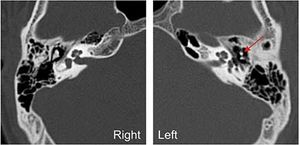

Post-traumatic Ossicular Dislocation

Case History: 20-year-old male with history of head injury followed by reduced hearing in the left ear.